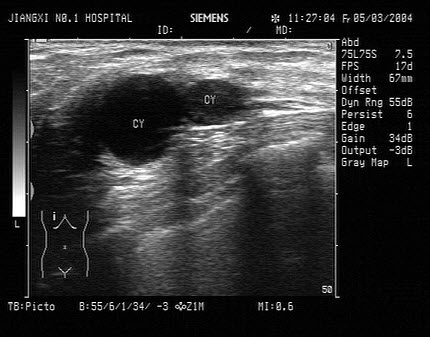

某患者右肾区疼痛数日,体温38℃。根据该患者右肾声像图表现,最可能的超声诊断为()

A.肾周围炎

B.肾炎

C.肾结石

D.肾结核

E.肾周血肿